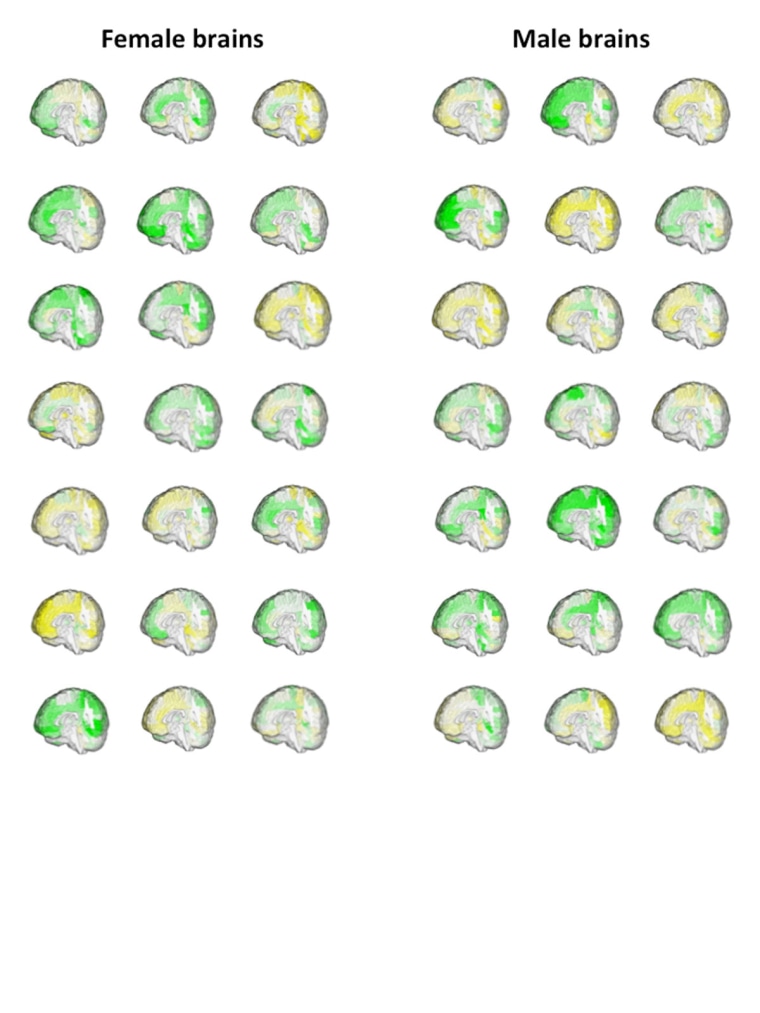

They couldn’t find any single pattern that distinguishes between a male brain and a female brain, and say only a very small percentage of people fall under clear all-male or all female brain patterns.

“Our study demonstrates that although there are sex/gender differences in brain structure, brains do not fall into two classes, one typical of males and the other typical of females, nor are they aligned along a ‘male brain–female brain’ continuum,” Daphna Joel of Tel Aviv University and colleagues wrote.

Joel’s team looked at magnetic resonance imaging (MRI) scans of the brains of more than 1,400 people of all ages from around the world, including Americans, Chinese, Germans and Australians.

They did find some regions of the brain that tended to indicate sex differences. But when they considered these regions together across all their brain scans, the picture just got muddy, they reported in the Proceedings of the National Academy of Sciences.

Anywhere between 23 percent and 53 percent of the MRIs had at least one region with a “male-end” score and one region with a “female-end” score, they found. And at the most, 8 percent of the brain scans showed someone whose brain regions all scored “male” or “female.”